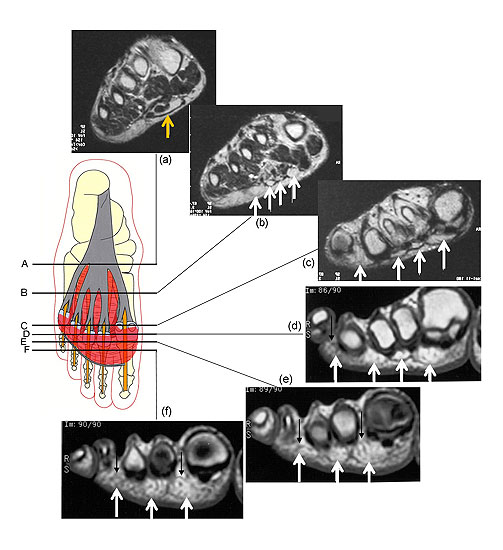

Die Plantaraponeurose besteht aus zwei Gewebeschichten. In Höhe des Metatarsaleschafts teilt sich die Plantaraponeurose in fünf kräftige Zügel, die durch Fettkörper separiert werden (Abb. 4). Weiter distal, in Höhe des Metatarsalehalses trennt sich dann die oberflächliche von der tiefen Schicht.

MRT Aufnahmen zeigen das plantare Fettpolster zwischen den beiden Schichten der Plantaraponeurose.

<div style="text-align:left">(a) In der sagitalen Schnittführung des MRTs ist erkennbar, wie die oberflächliche und die tiefe Schicht der Plantaraponeurose

Abbildung 5

Die tiefen Ausläufer spalten sich dann weiter in einen medialen und lateralen Zügel. Diese und ziehen dorsal um die Sehnenscheide der Flexoren mit Ausläufern in die plantare Platte und in die tiefen intermetatarsalen Ligamente. In diesem Bereich vereinigen sich die proximalen Ausläufer des plantaren Fettpolsters zu einer einheitlichen Struktur, die den Raum plantar der Metatarsophalangealgelenke und Grundphalangen über die gesamte Breite des Vorfußes ausfüllt. Zur Fußsohle hin begrenzt die der Haut aufliegende, oberflächliche Schicht der Plantaraponeurose das plantare Fettpolster. Distal davon zieht das Fettpolster nach dorsal und ist an den Grundphalangen, den Sehnenscheiden der Flexoren und den dazwischen liegenden Bandstrukturen fixiert (Abb. 5).

MRT Aufnahmen und Skizzen zur Demonstration des Effekts der Belastung auf den Vorfuß und das plantare Fettpolster. Dargestellt sind die verschiedenen Phasen des Gangzyklus.

<div style="text-align:left">1. Beim Fersenaufsatz befinden sich die Zehengrundge

Abbildung 6

Die aus dem Reversen Windlass Mechanismus resultierende plantar flektierende Kraft ist direkt proportional zur Lastaufnahme des korrespondierenden Strahls 3.  Der Aufbau des plantaren Fettpolsters aus vielen septierten Fettzellen unterstützt die Druckverteilung unter den Metatarsaleköpfen auf ein relativ großes Areal des plantaren Fettpolsters. Der reverese Windlass Mechanismus führt dazu, dass auch proximale Anteile der Zehe relevante Anteile der Last aufnehmen (Abb. 6). Bei einem gesunden Fuß wird so sichergestellt, dass das plantare Fettpolster, die Haut und die plantare Platte beim Abrollvorgang ihre Position nicht verändern. Alle diese Mechanismen sind beim Rheumapatienten mehr oder weniger stark zerstört.